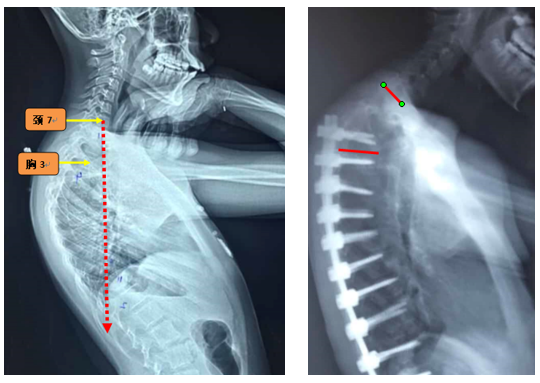

(3)上固定椎位于T1-3

图7 术前-术后1个月-术后1个月外观

Ø 颈7铅垂线距离UIV太远

图19 颈7铅垂线距离UIV太远

1.选择合适的UIV

(1)固定近端交界性后凸角>5°的区域应包括在融合区内;

(2)胸椎后凸过大患者,融合水平应跨过胸椎后凸节段到上胸段;

(3)尽量跨过交界区,如胸腰段尽量不终止于T11和T12;

(4)颈7铅垂线距离UIV不要太远;

(5)矢状面上UIV上方椎间隙无后凸角度。

图23 选择合适的UIV